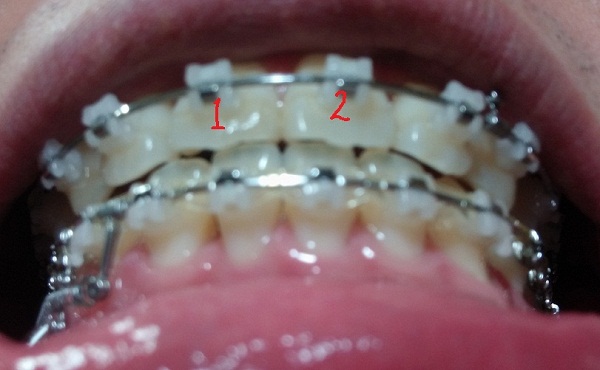

[아래서 본 정면1]

[아래서본 정면2]